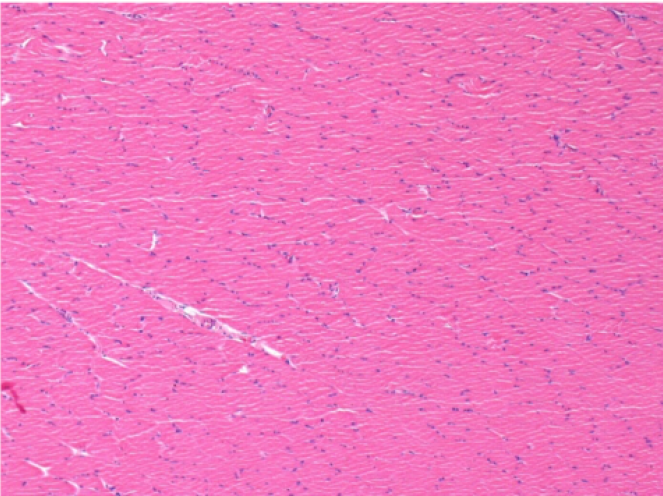

10 días después de la inyección de Endopeel 0,1 ml en el músculo pretibial derecho.

Aquí puede ver la formación de las vacuolas que están rodeadas de linfocitos. Las vacuolas son diferentes a la necrosis tisular. La presencia de linfocitos está relacionada con la permeabilidad de las membranas celulares.

07